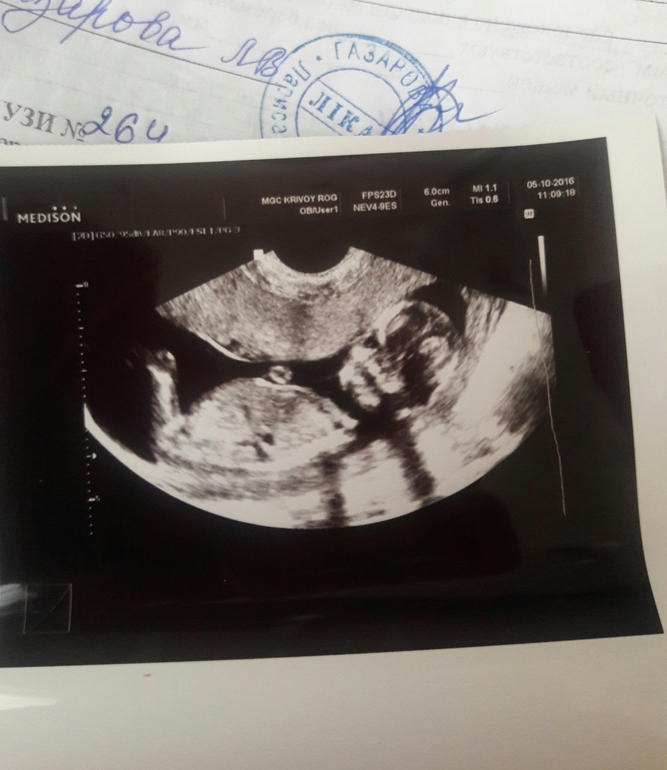

Узи 13+5

УЗИ, КТГ, доплерЭто малышу там тесно, что головка с двух сторон сдавлена? Это не страшно? И пол не видно?

Полового бугорка не видно,поэтому и пол тоже.Если про тонус ничего не говорили значит такой ракурс снимка

Ой какая красоточка!!! Похоже на девочку.... тонус если был бы, то вам сказали бы. Все хорошо у вас, ттт!

А про пол по-моему: методом исключения, мальчика не видно, значит девочка))))